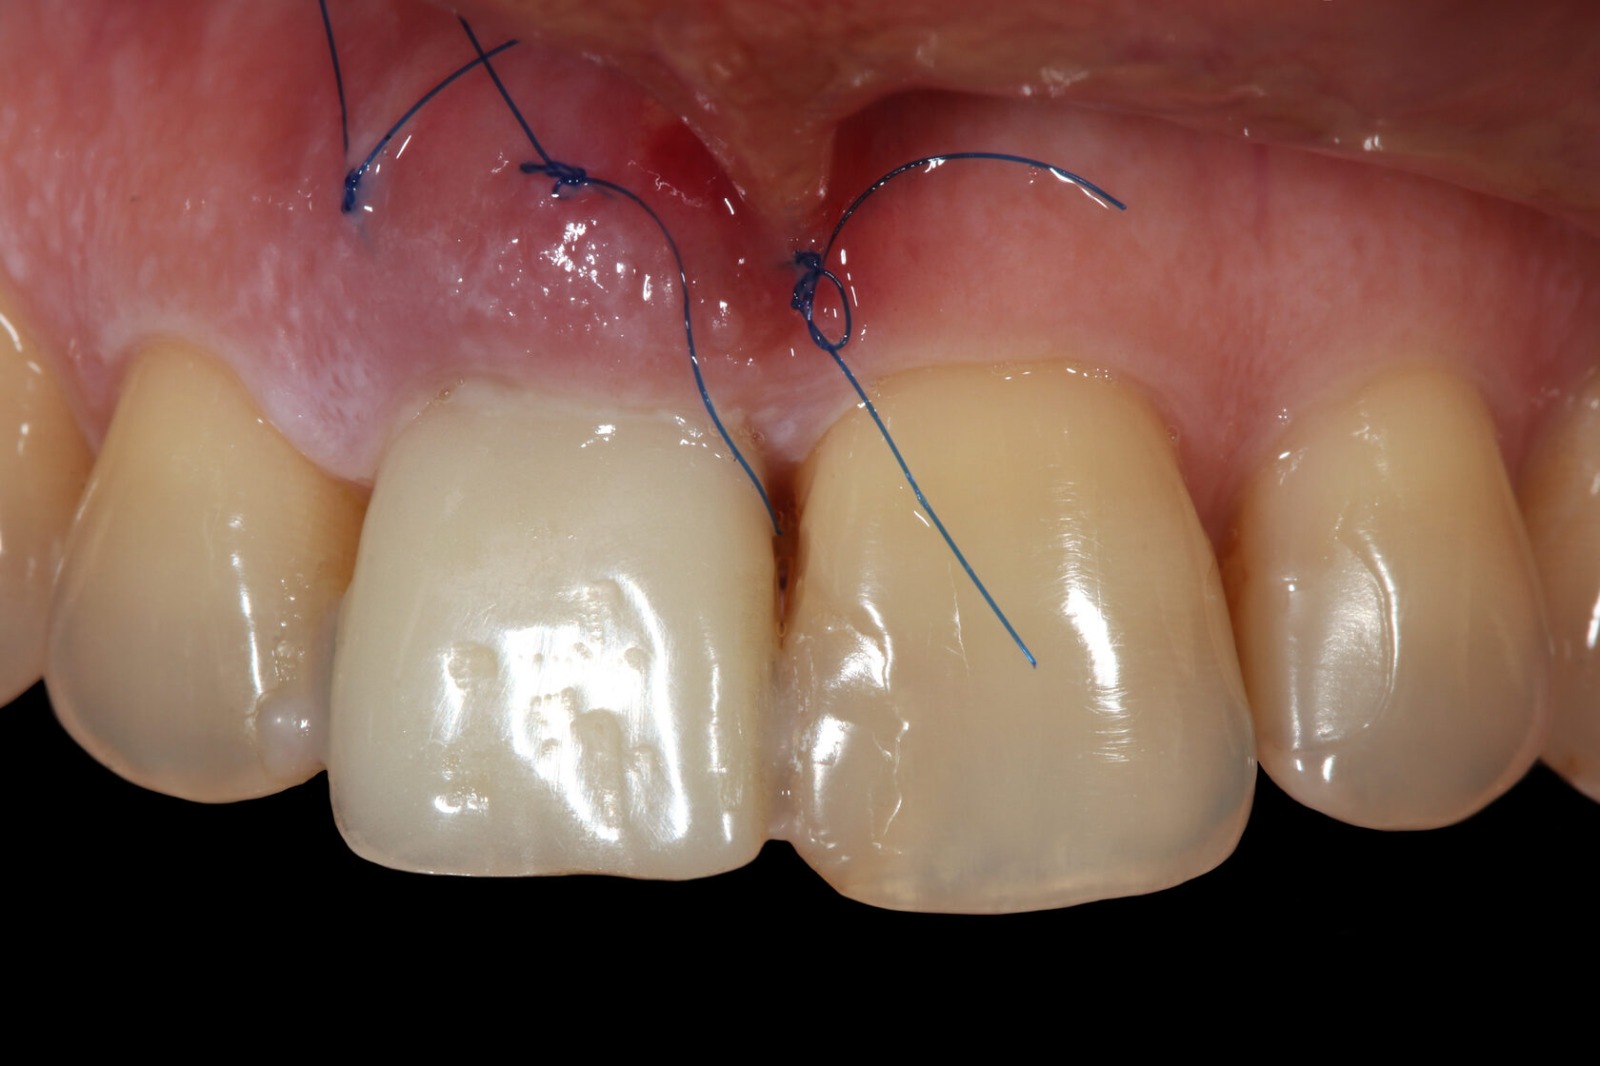

Фотографии учебного материала